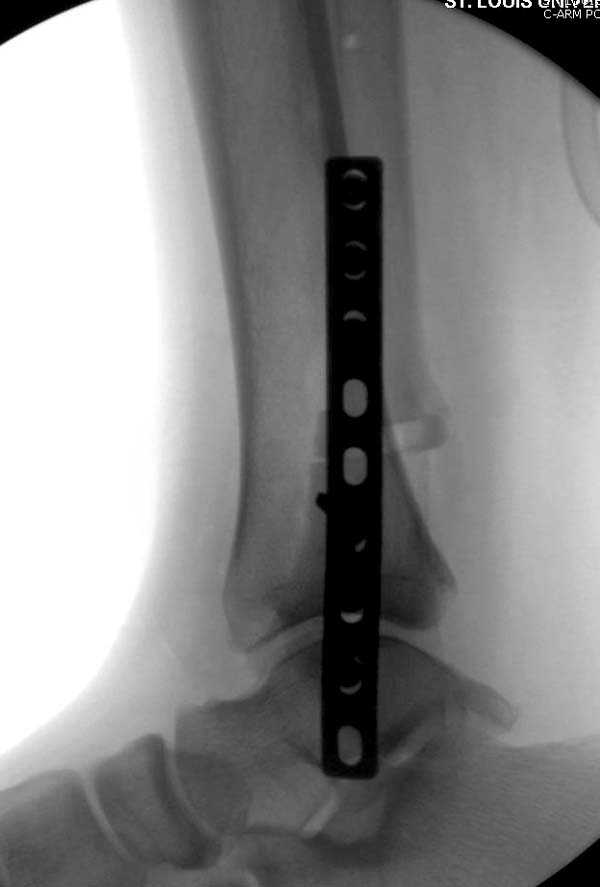

Здесь представлено решение похожей проблемы. Больной в течение года

лечился консервативными мерами, и боли в голеностопе были основным

показанием к операции.

Проведена обычная стандартная процедура по исправлению

неудовлетворительного состояния голеностопного сустава, где кроме

удлинения малоберцовой с применением compression tension device за

проксимальный конец пластины, проведено замещение трикортикальным

графтом из крыла, освобождение синдесмоза и медиальной щели от

фибротических масс с фиксацией.